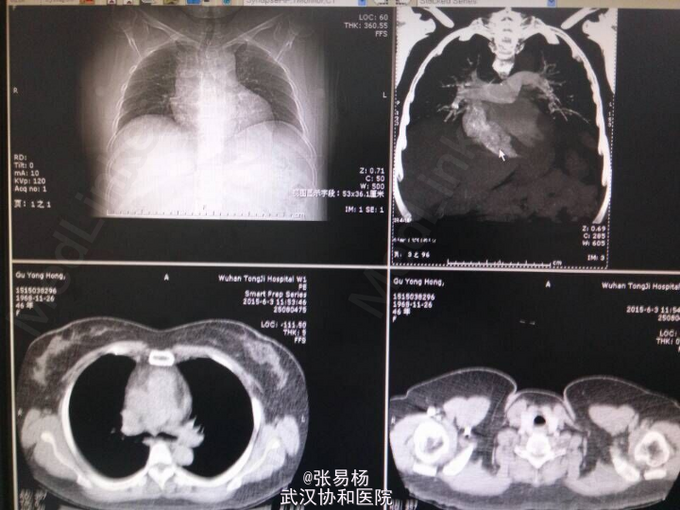

查体:双下肢水肿,指压征阳性,余无特殊。 辅检:肺动脉血管成像,CT-三维成像示:左肺动脉及其分支,右肺上叶肺动脉及其分支,右肺下叶后段肺动脉充盈缺损,考虑栓塞双肺血管纹理增强,考虑灌注不足所致。